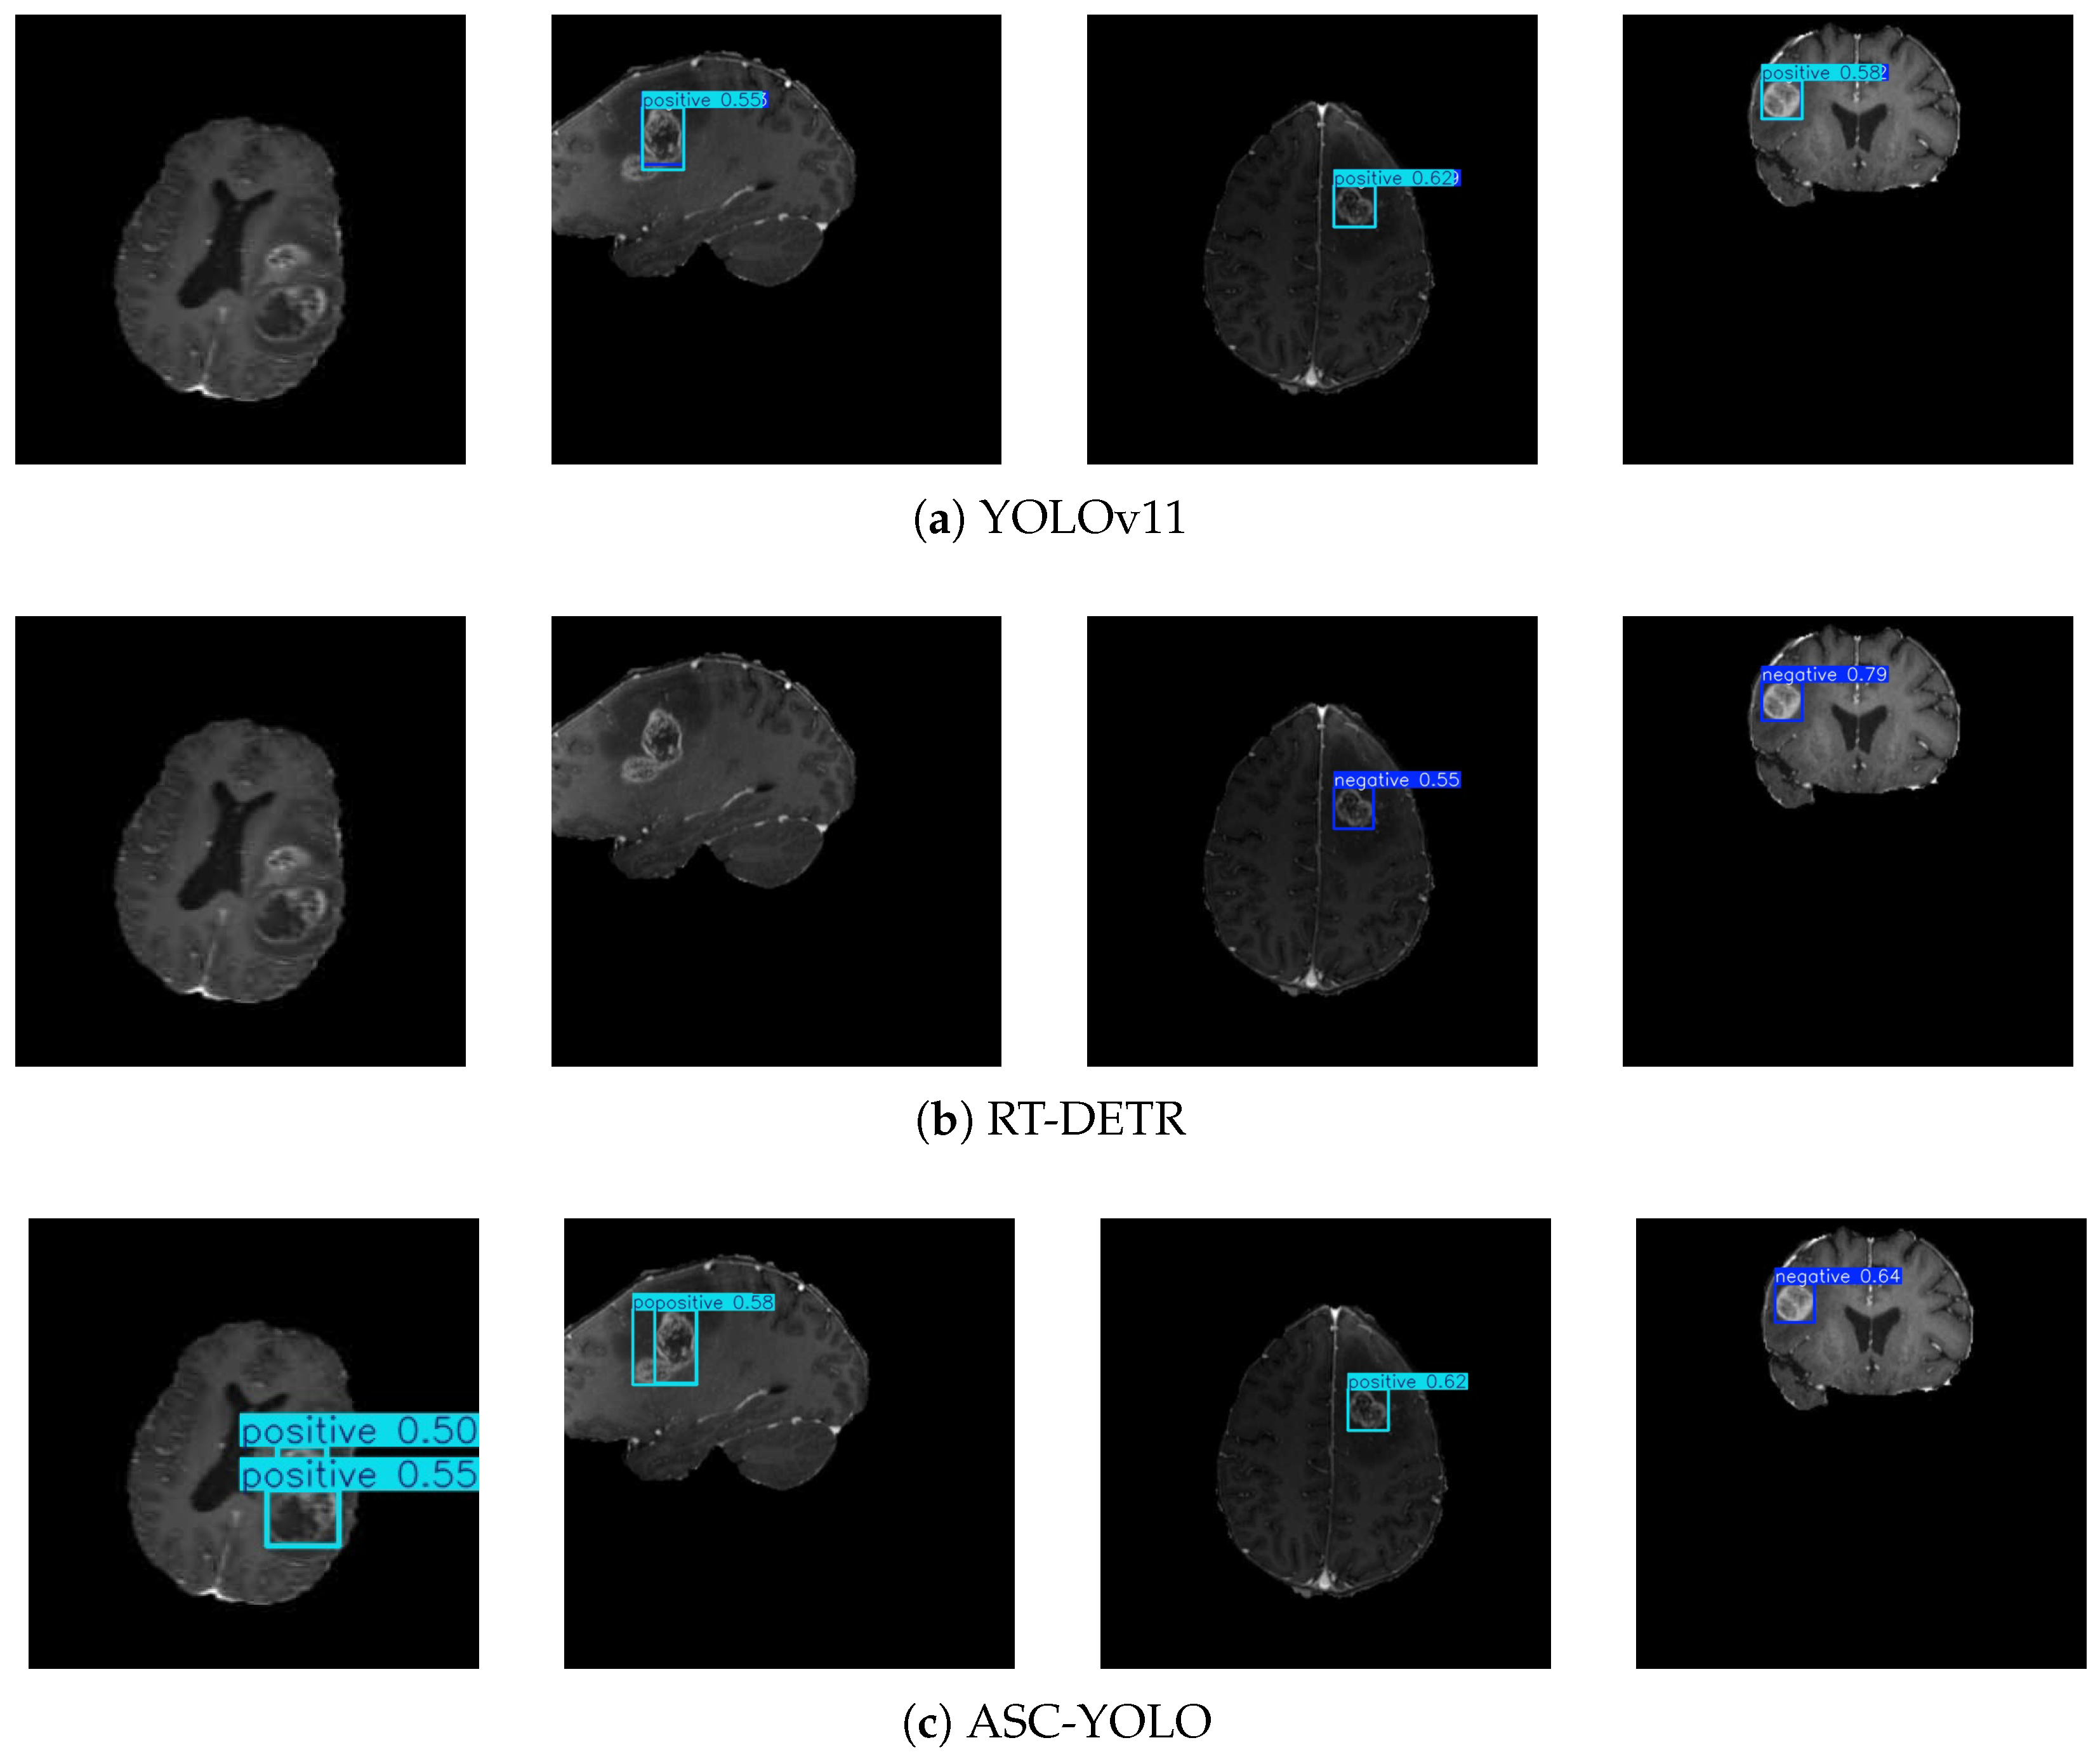

3.3. Generalization Analysis

3.3.1. Dataset Preparation

3.3.2. Results of the Experiment

| Models | Parameters | Recall | mAP@50 | mAP@50-95 |

|---|---|---|---|---|

| YOLOv11 | 5.1 | 0.520 | 0.532 | 0.343 |

| RT-DETR | 8.3 | 0.490 | 0.501 | 0.309 |

| ASC-YOLO | 2.9 | 0.550 | 0.602 | 0.412 |